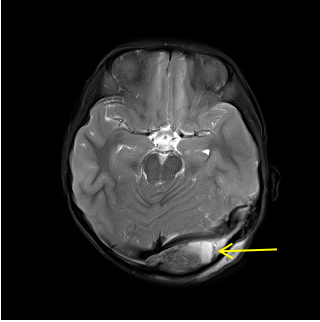

• 妙手回春---市三医院神经外科成功救治两名危重脑外伤患儿

妙手回春---市三医院神经外科成功救治两名危重脑外伤患儿 2020-10-26 国庆长假期间,很多人利用难得假期家人团聚、出行游乐,但在游乐过程中一定要注意安全,特别是家有小孩的家庭,一定要做好安全防范,以免发生意外。国庆节期间,我院神经外科就收治了一名坠落导致头颅硬膜外血肿合并颅骨骨折的小女孩,令人心疼,所幸经过神经外科团队的成功施…